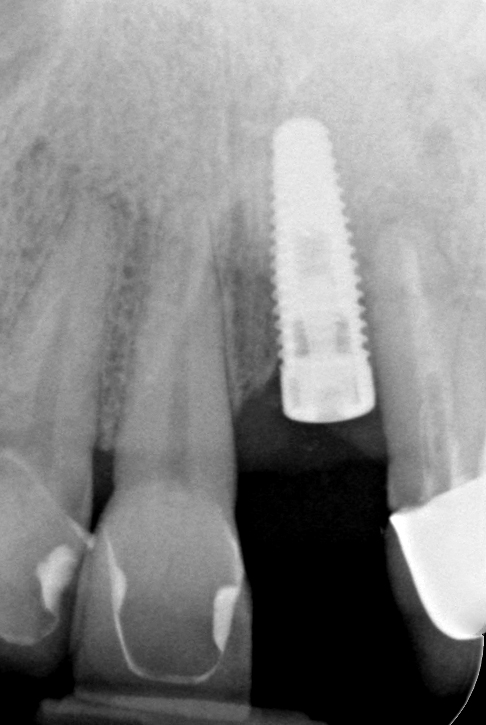

Fig 17. Radiograph showed symmetrical infrabony defect affecting 50% of the implant surface.

Figure 17

Clinical examination showed 2 mm of buccal recession with a shallow vestibule and absence of keratinized attached gingiva against the crown with 8 mm of circumferential pocketing accompanied by bleeding upon probing (Figure 15 and Figure 16). A periapical radiograph showed a symmetrical vertical osseous defect causing the loss of 50% of the bone around the implant (Figure 17). Because the patient had made a significant investment of time and finances to replace her lost tooth with the implant, she desired that the implant and restoration be retained, if feasible.